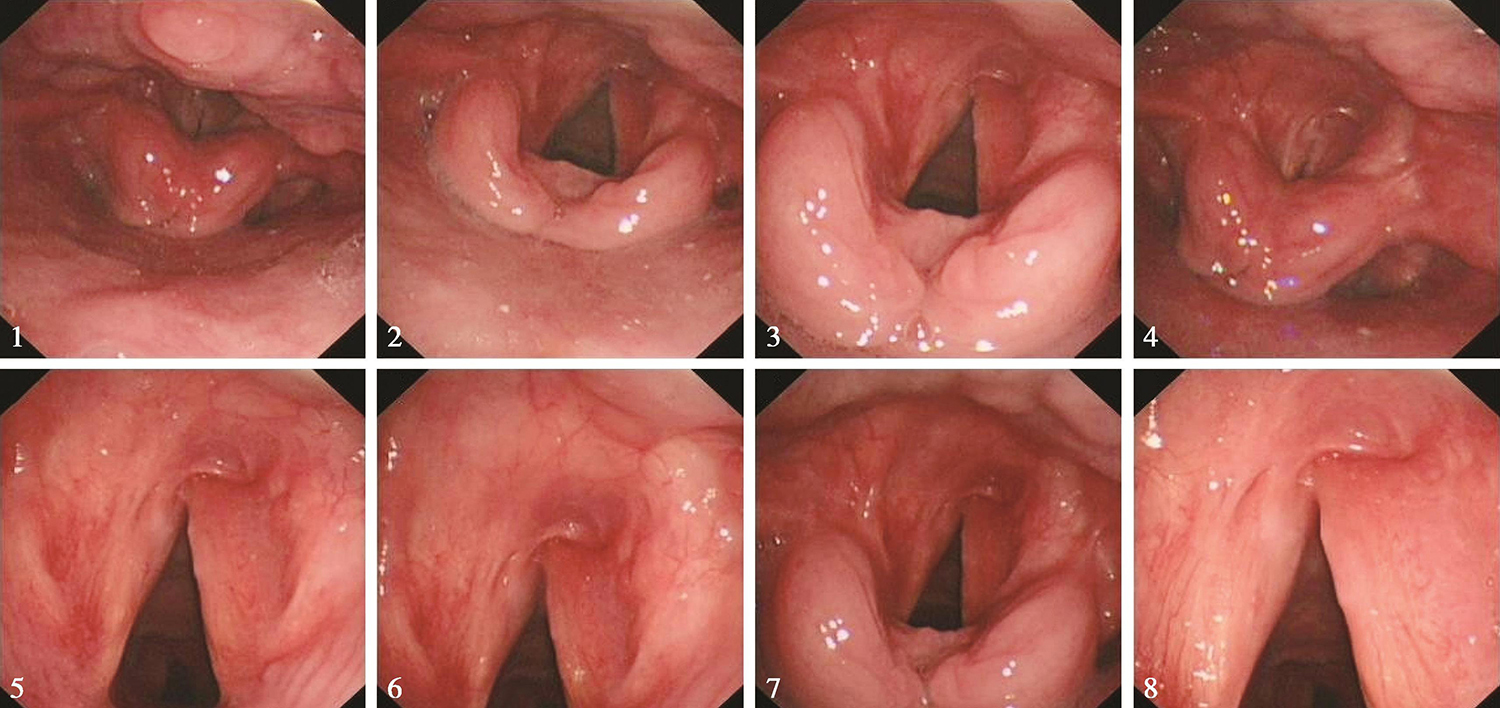

7.2017年11月1日喉癌术后颈胸CT复查,参阅术前2016年11月28日CT图像,所见如下:

(5)右肺上叶后段多个结节较前增多、增大,部分融合成团,现大者最大截面约2.4cm×1.8cm(图5),需高度警惕恶性,转移瘤或原发肺癌待鉴别,请结合临床,建议活检。余双肺可见多发小结节,部分为新出现,大者约0.4cm,转移瘤可能性大。

图5 右肺上叶后段多个结节较前增多、增大

(6)纵隔见多个淋巴结,较大者约0.9cm。

(7)双侧胸腔及心包未见积液。

(4)右肺上叶后段多个结节较前缩小,现大者约1.5cm×0.8cm(图6),请结合临床并随诊。余双肺可见多发小结节,较前缩小,大部分已显示不清,现大者约0.2cm,建议随诊。

图6 右肺上叶后段多个结节较前缩小

12.2018年2月24日颈胸部CT,“喉癌术后、右肺鳞癌化疗后”复查,与2018年1月11日颈胸部CT图像比较。

(2)右肺上叶后段不规则结节,余双肺多发微结节(图7),均同前大致相仿,建议继续随诊。

图7 右肺上叶后段不规则结节